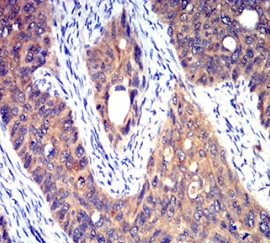

HTR3A Mouse Monoclonal antibody[3B11]

The product of this gene belongs to the ligand-gated ion channel receptor superfamily. This gene encodes subunit A of the type 3 receptor for 5-hydroxytryptamine (serotonin), a biogenic hormone that functions as a neurotransmitter, a hormone, and a mitogen. This receptor causes fast, depolarizing responses in neurons after activation. It appears that the heteromeric combination of A and B subunits is necessary to provide the full functional features of this receptor, since either subunit alone results in receptors with very low conductance and response amplitude. Alternatively spliced transcript variants encoding different isoforms have been identified.

Immunogen:    Purified recombinant fragment of human HTR3A (AA: extra 24-157) expressed in E. Coli.